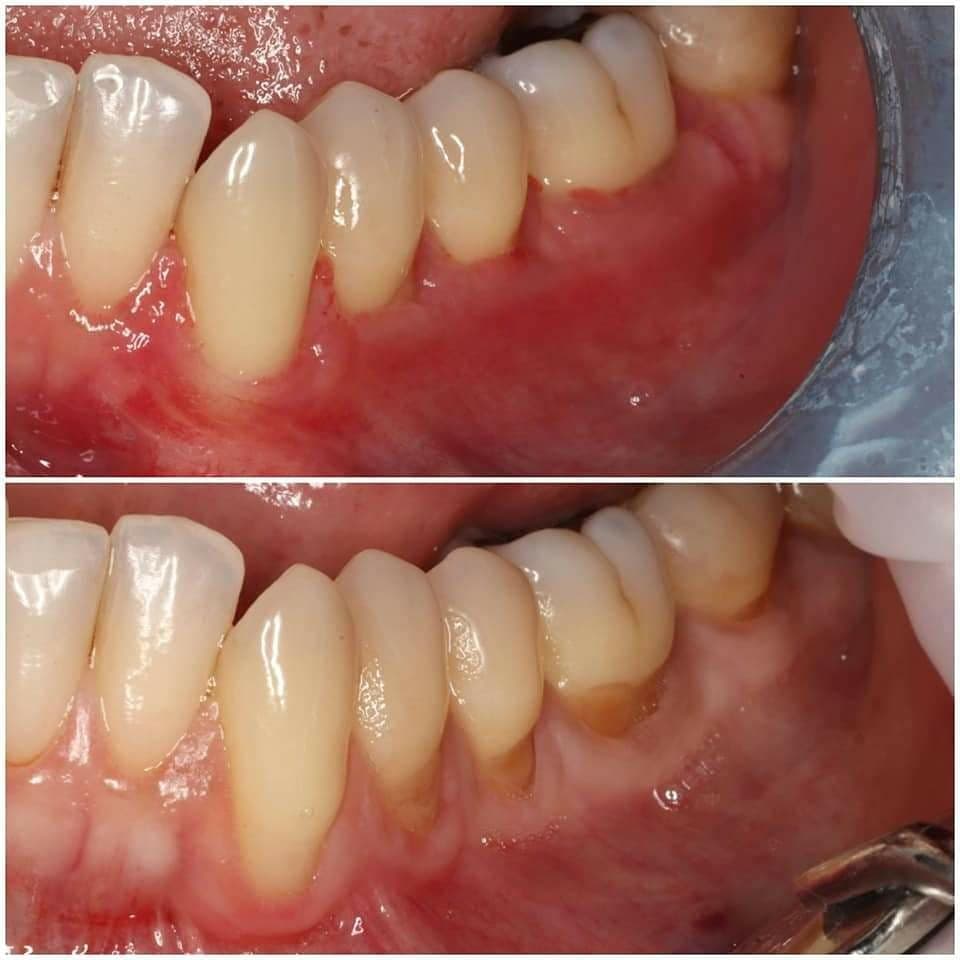

Contrôle à 14 jours, Zuchelli Style

Zone nettoyée curettes, piezo, fraises diamantés, EDTA.

Lambeau Zuchelli, avec décharge verticale en mésial.

Greffon palatin, dé-épithélialisé avec lame 15, sashimi style.

Sutures PGA 7-0 pour le greffon

Sutures Prolene 6-0 pour le lambeau

J'imagine qu'avec les fraises diamantés tu as adouci le bombé vestibulaire?

oui, adoucir la jonction racine/email